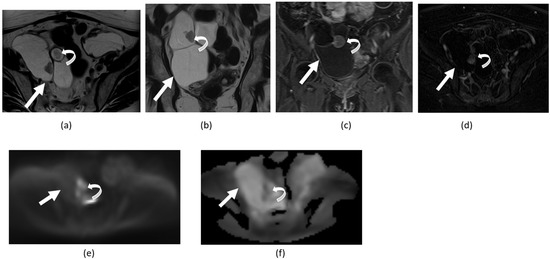

3.3. Endometriosis